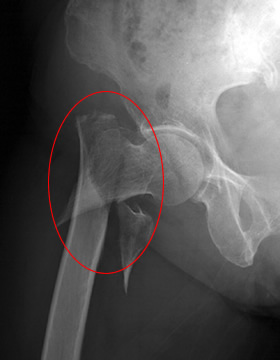

寝たきり原因・第2位の骨折は、70%が大腿骨頸部骨折で、その原因の95%は転倒によるものといわれいます。

![]() |

| 大腿骨頸部骨折レントゲン | 大腿骨頸部骨折イラスト |

1987年、1992年、1997年に行われた、大腿骨頸部骨折全国頻度調査報告によると、寝たきりの原因となる大腿骨頸部骨折の大半は転倒や転落が原因であり、骨粗鬆症とも関連があることが明らかとなりました。大腿骨頸部骨折新患者数は1987年と1997年を比較して1.7倍も増加していたとのこと。

また別の調査では、骨粗鬆症は女性に多いこともあり、大腿骨頚部骨折の発生率は男性対女性では1:3。なんと、女性が男性の約3倍!!

『転倒による、大腿骨頸部骨折(股関節骨折)で寝たきりになる女性が多い』

というわけです。